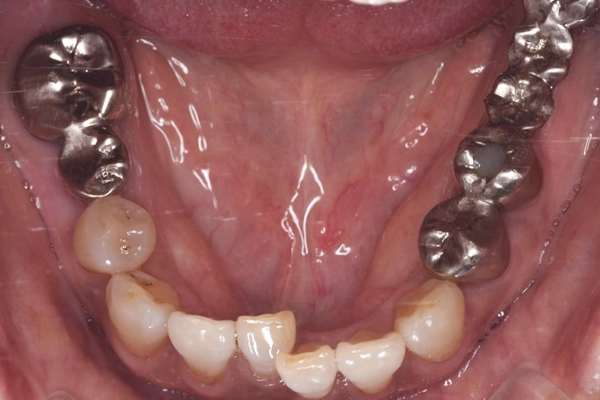

治療前の下顎の様子

です。

矯正を行ったことで、前歯のガタガタ綺麗にすることができました。